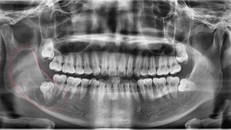

Thanh niên Hà Nội tưởng mọc răng khôn, bác sĩ lôi ra ‘thủ phạm’ trong miệng

Nam thanh niên nghĩ mình mình mọc răng khôn vì thường xuyên sưng đau vị trí gần răng số 7. Tuy nhiên khi khám chuyên sâu, bác sĩ phát hiện ‘thủ phạm’ ẩn giật.